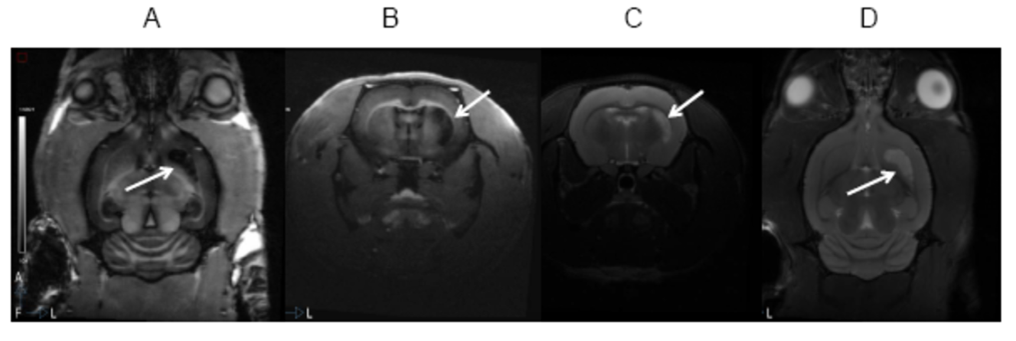

Fig. 3. A y B) corte coronal y axial potenciado en T1, C y D) corte axial y coronal potenciado en T2.

Si estudiamos la figura 3, tenemos 4 imágenes, dos de las cuales están potenciadas en T1 (A y B) y en T2 (Cy D). La lesión corresponde a una isquemia cerebral producida por oclusión de la Arteria Cerebral Media. La lesión es hipointensa en T1 pero sin embargo es hiperintensa en T2. ¿Cuál de las dos proporciona mayor información? La imagen potenciada en T2. Ya que con esta se puede distinguir perfectamente la lesión con respecto a los tejidos de alrededor.